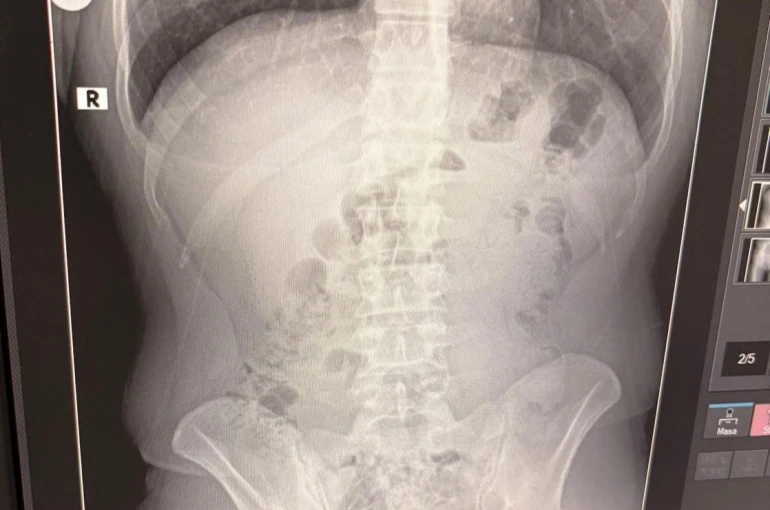

Adreste yapılan arama sırasında ekipler, şüphelilerden birinin üstünde 1 adet kapsül ele geçirdi. Şüphe üzerine tüm şüpheliler hastaneye götürüldü ve yapılan röntgen kontrollerinde 3 kişinin midelerinde kapsül içine gizlenmiş metamfetamin tespit edildi.

Hastanede tedavi altına alınan şüphelilerin vücudundan kapsüller çıkarılırken, adreste ele geçirilenlerle birlikte toplam 1 kilo 516 gram metamfetamin ele geçirildi.